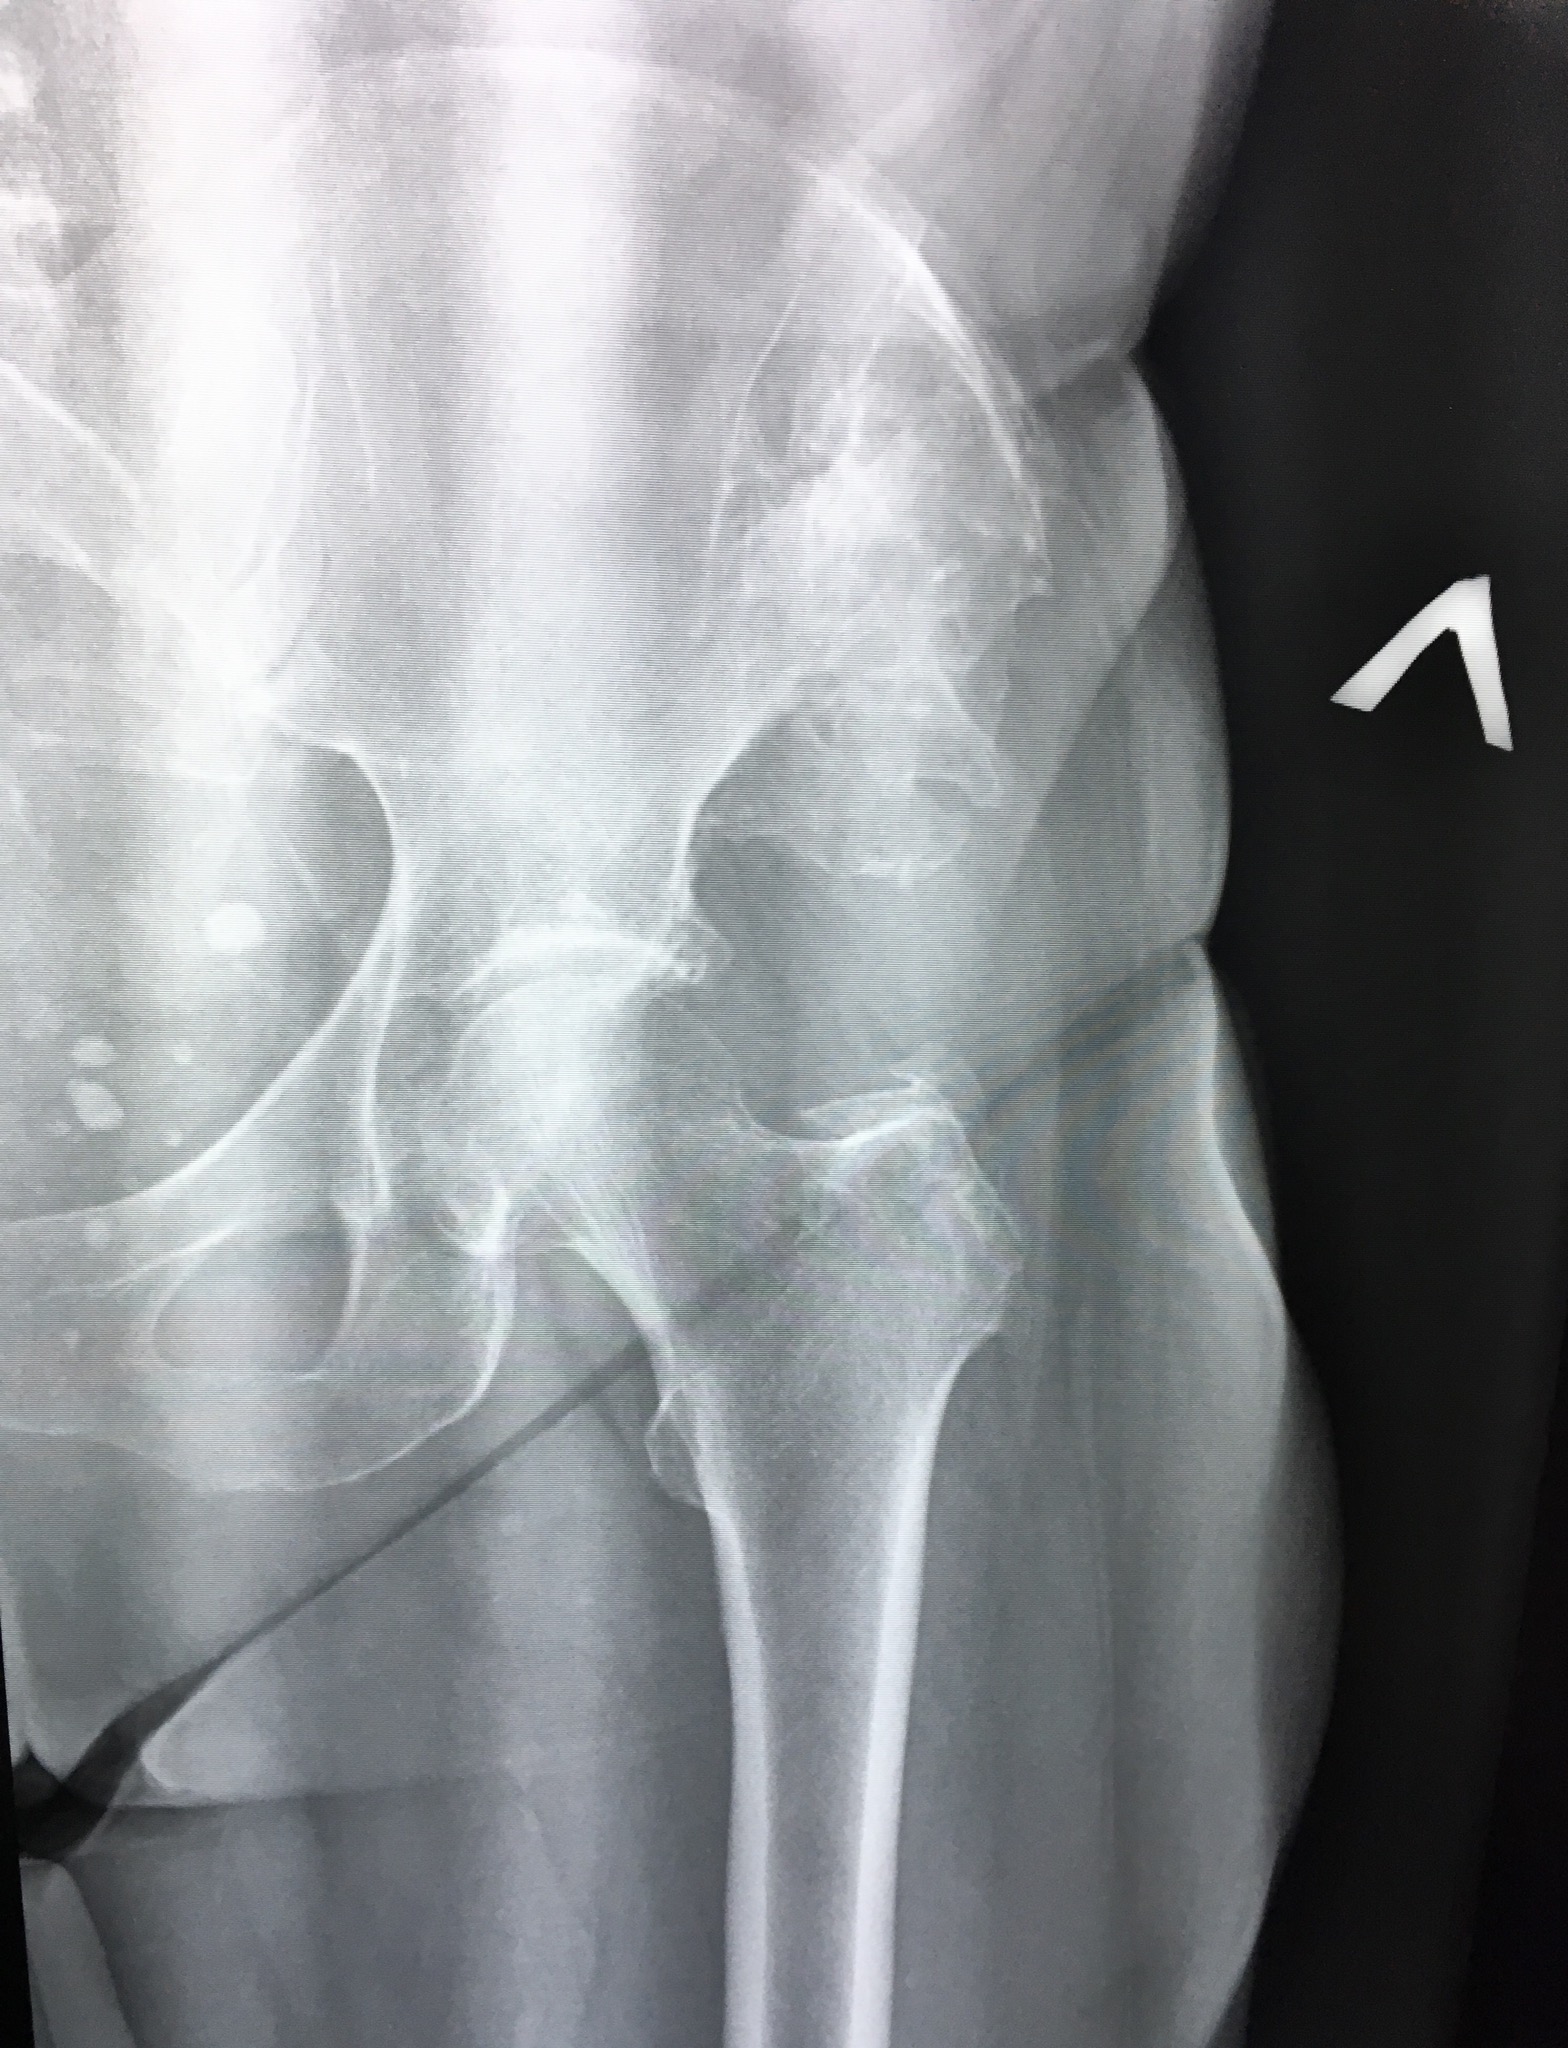

209. Тазобедренный сустав

Коллеги, помогите ,пожалуйста , описать картину крыла подвздошной кости.

Тип: Клиническое наблюдение

Область: Скелетно-мышечная система

Модальность: Rg

Дата: 16.09.2019 - 11:41